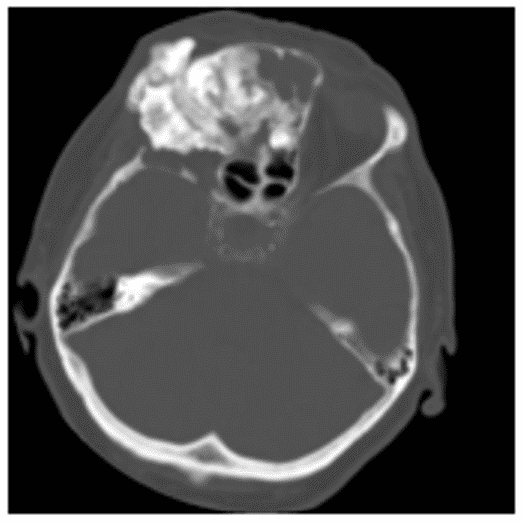

Остеобластома на КТ обычно представлена сочетанием плотной кости и участков затемнения (рисунок 4).

Рис. 4. КТ черепа, аксиальная плоскость. Гигантская остеобластома, распространяющаяся в правую орбиту, полость носа и переднюю черепную ямку

Данные КТ позволяют определить признаки локально агрессивного роста остебластомы, место ее исходного роста, наличие/отсутствие распространения опухоли за пределы околоносовых пазух.